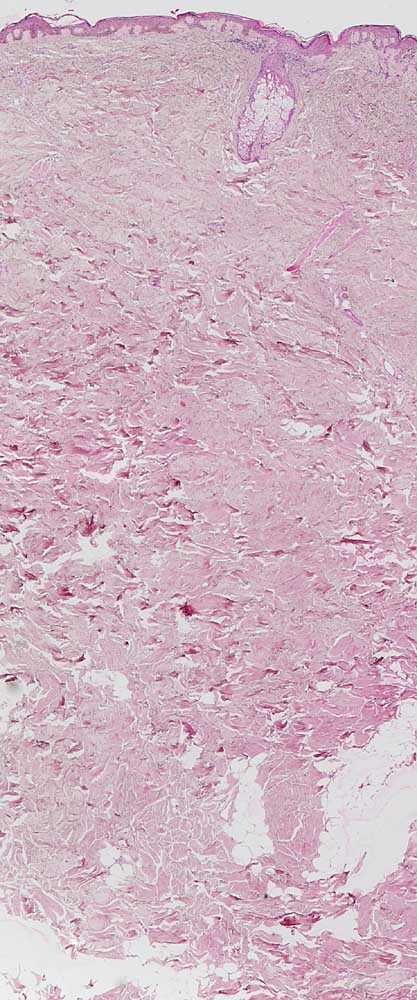

Chronische Radiodermatitis

Therapiefolgen

Haut

Haut, Rumpf

Pathologischer Befund